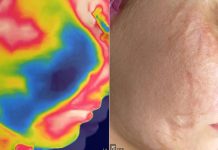

Blizna w gabinecie kosmetologicznym. Termografia i wybrane terapie

Blizny to zmiany, będące skutkiem uszkodzeń skóry. W zależności od ich pochodzenia, wymienia się blizny: pourazowe, po oparzeniach, chirurgiczne, potrądzikowe. Również nieprawidłowe wykonanie zabiegów...